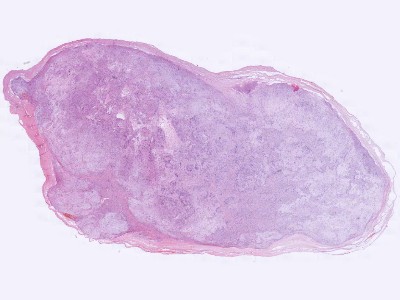

Histologie Schwannoma Histologie Schwannoma

Bron hoge resolutie PA-foto's: Kevin Kwee en Afdeling Pathologie MUMC. Klik op de afbeelding om in te zoomen.